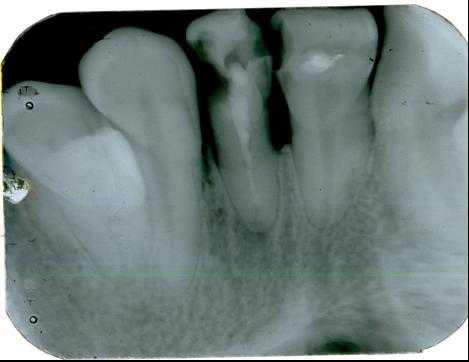

Рис. 1. Диагностический и измерительный снимки зуба 36, выполненные в прямой (а) и дистально-эксцентрической проекции (б). 36 — хронический апикальный периодонтит (К04.5) с характерными изменениями на мезиальном корне.